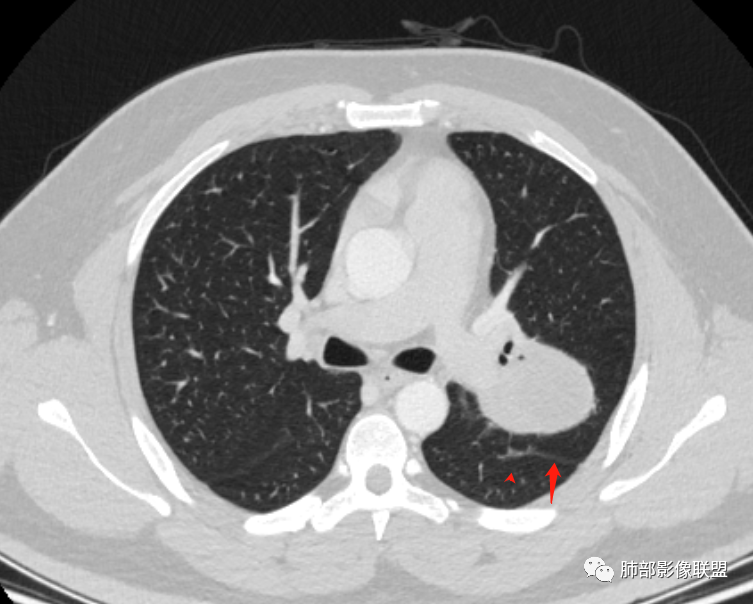

下叶基底干支气管受压下移

下叶背段支气管受压稍后内移位,通畅

就是支气管目前基本没有堵塞,只是受压

空气新月征:

青年男性,体检发现左肺不规则类圆形占位性病变,叶间裂区域,定位胸膜来源。左肺下叶支气管受压狭窄,但管壁光整,未见腔内阻塞或管壁受侵。包块边界清晰,浅分叶,内部密度不均匀,病灶后份见空气新月征。渐进性强化,增强动脉期见分支状血管,蛇纹血管征。肺门纵膈未见增大淋巴结,符合孤立性纤维瘤(SFT)。